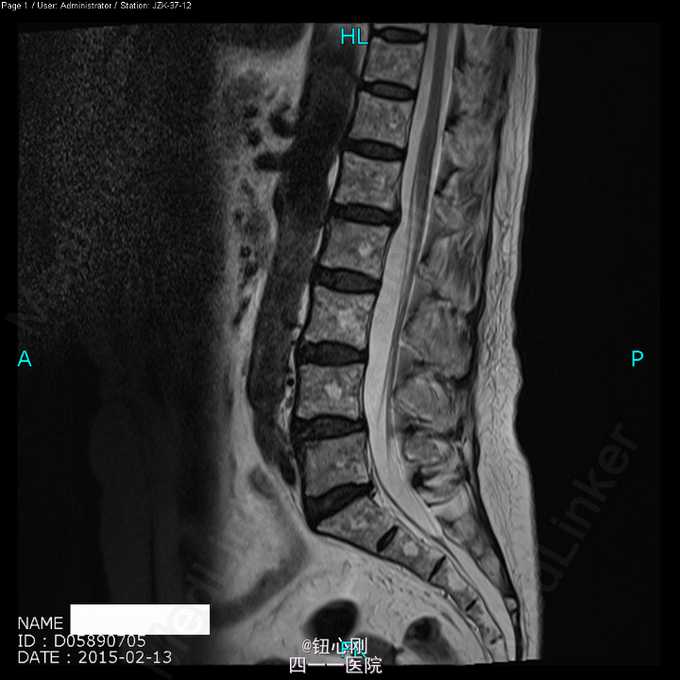

患者, 女,66岁。 主 诉:反复颈肩部麻木感10余年,腰骶痛3月余。 现病史:患者缘于10年前无明显诱因下出现双侧颈肩部轻微麻木及不适感,给予按摩等理疗后好转,此后每年不定期反复发作,未予重视,2月前患者在搬重物后出现腰痛症状,弯腰不能,予以针灸等理疗,症状有所改善。2015年2月13日来我院就诊,行脊柱MRI及PET-CT扫描示:颈6、胸12、腰2、4、5椎体转移瘤?

体检未见明显阳性体征。 辅助检查:血沉68mm/h,神经元特异性烯醇化酶23ug/l,余肿瘤指标正常。三大常规、肝肾功、电解质正常。 颈椎MRI、腰椎MRI及PET-CT扫描见图。

术前诊断:多椎体病变待查(转移瘤?) 诊断依据:老年女性,出现颈腰部疼痛,MRI及PET-CT扫描提示椎体多节段病变,以转移瘤可能性为大,同时血沉升高。 处理:2015-03-31在全麻下行颈6椎体病变前路次全切+钢板钛网植骨融合内固定术。术中所见:颈6椎体骨质疏松,部分硬化,未见鱼肉样组织。术后切除骨质送病理检查。 病理报告:骨小梁稀疏,其间有纤维组织,同时可见硬化死骨。 术后诊断:颈6椎体骨质疏松性骨坏死。

随着医学影像学及脊柱微创手术的发展,骨质疏松性椎体骨坏死逐渐被认识。该病临床上并非少见,骨坏死会导致椎体逐渐塌陷与进行性后凸畸形,引起患者长期腰背痛,甚至出现脊髓神经受压而瘫痪。患者为老年,主诉脊柱疼痛,MRI有椎体信号改变,因而易与脊柱转移性肿瘤混淆。骨坏死椎体在T1WI加权像上呈界限清楚的低信号区域,在T2WI加权像及脂肪抑制序列像上呈界限清晰高信号区域。这是与脊柱转移性肿瘤相鉴别的要点,对于累计整个椎体的骨坏死更需注意鉴别。 如疼痛不缓解或发生后凸畸形,可行椎体后凸成形术。